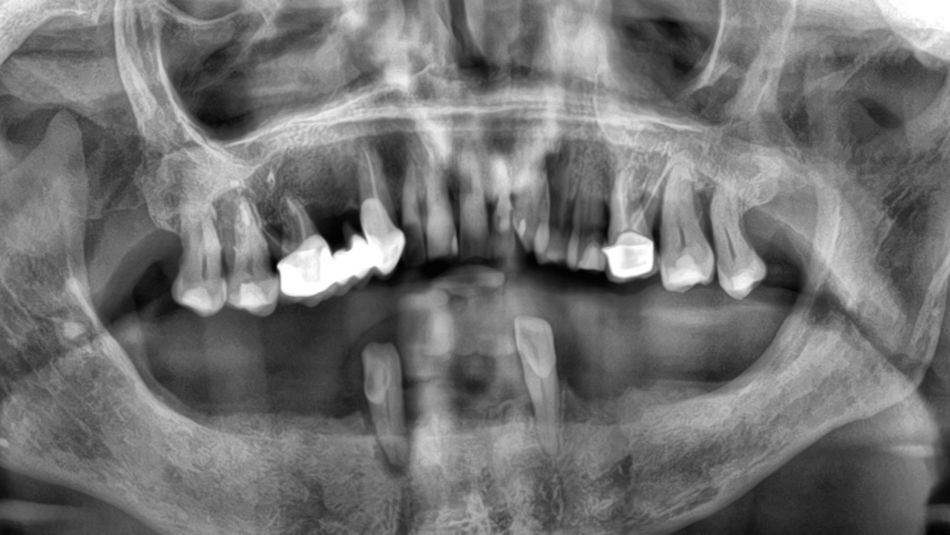

1a. 1b. Pre-operative panoramic X-ray and CBCT showing moderate generalised bone resorption in the mandible, a reduction in vertical dimension in the posterior region and the planned positioning of mini- implants.

1a

1b